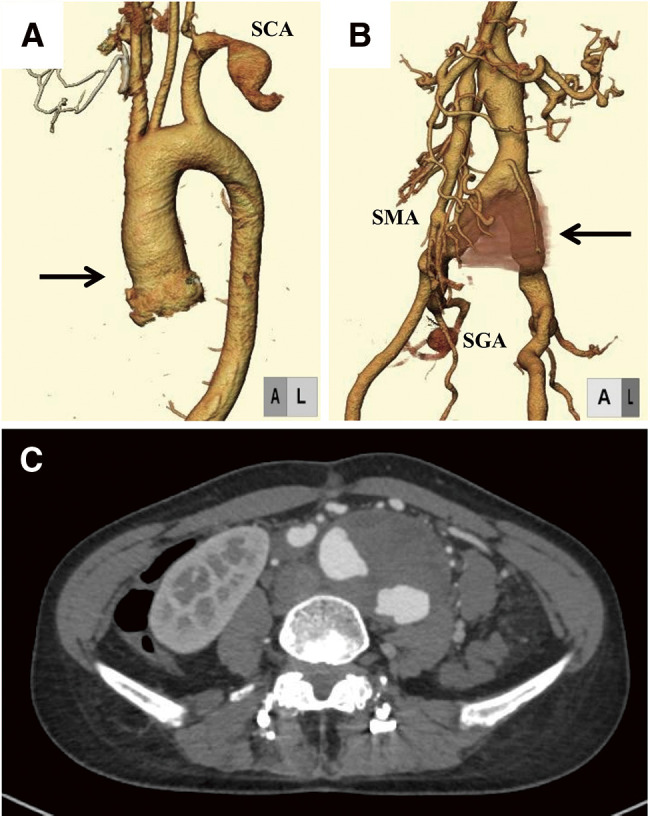

Loeys-Dietz syndrome (LDS) is a genetic connective tissue disorder associated with vascular involvement and craniofacial, skeletal, and cutaneous abnormalities. Herein, we describe the case of a 28-year-old female who presented with a pulsatile mass in her abdomen. Imaging studies revealed multiple aneurysms, including a 53-mm abdominal aortic aneurysm (AAA) and tortuosity of the intracranial arterial vasculature. Genetic testing revealed a mutation in transforming growth factor beta receptor 1, leading to a diagnosis of LDS. The patient underwent open surgical repair of AAA. Other arterial lesions were carefully followed. This case demonstrates that AAA can be a primary manifestation of LDS.